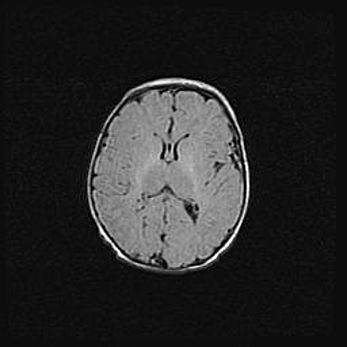

Лейкомаляция с кистозно-глиозной дегенерацией головного мозга.

Возраст: 2 месяца 25 дней

Вес: 6400 г

Окружность головы: 40 см

Срок гестации: 41 неделя

Лейкомаляцию относят к ишемически-гипоксическим повреждениям головного мозга, диагностируемым у новорожденных. При лейкомаляции в головном мозге обнаруживают очаги некроза, возникшие после тяжелой гипоксии и нарушения кровотока. В процессе морфогенеза очаги проходят три стадии: 1) развития некроза, 2) резорбции и 3) формирования глиозного рубца или кисты. Перивентрикулярная лейкомаляция (ПЛ) встречается примерно в 12% случаев среди новорожденных, обычно – у недоношенных детей, причем, частота ее зависит от массы, с которой младенец появился на свет. Наибольшее число малышей страдает лейкомаляцией, если масса при рождении 1500-2500 г.